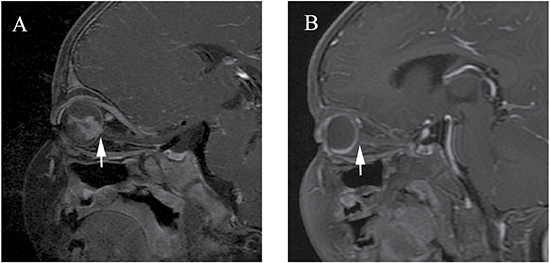

Figure 3: Clinically diagnosed retinoblastoma in a 16-month-old male (patient 3). Oblique sagittal contrast-enhanced T1-weighted, fat-saturated MRI shows abnormal nodular enhancement (arrow) of the postlaminar optic nerve (A), a finding indicative of postlaminar optic nerve invasion. After three cycles of intra-arterial chemotherapy (IAC), the abnormal nodular enhancement of the postlaminar optic nerve disappeared (B).

Optic nerve invasion is one of the primary histopathological risk factors due to its association with a high mortality rate. Surgical treatment is always preferred if there is evidence of optic nerve invasion [4, 23, 24]. Abnormal optic nerve (prelaminar or postlaminar) enhancement is generally regarded as a high risk of optic nerve invasion, especially postlaminar enhancement [4, 24]. The sensitivity and specificity of MRI for depicting postlaminar optic nerve invasion were reported to be approximately 50%−69% and 65%−90%, respectively [4, 23–27]. However, false positive findings of optic nerve enhancement without postlaminar optic nerve invasion have been reported for tumors, causing bulging of the lamina before invading the optic nerve beyond the lamina cribrosa [25, 28], or secondary to inflammation of the optic disc [4, 24], leading to the use of more conservative treatment approaches [29, 30] In our study, six patients with nodular enhancement of the postlaminar optic nerve underwent conservative treatment with IAC rather than enucleation, at the request of their parents. These cases showed significantly deceased nodular enhancements of the postlaminar optic nerve after IAC. We suggest that the drug could have also reached the minimal tumor foci through the blood vessels to the pre- and postlaminar optic nerve. No recurrences and metastases were found in the high-risk patients, with follow-ups of > 8 months, using monthly ophthalmoscopy and quarterly MRI examinations.